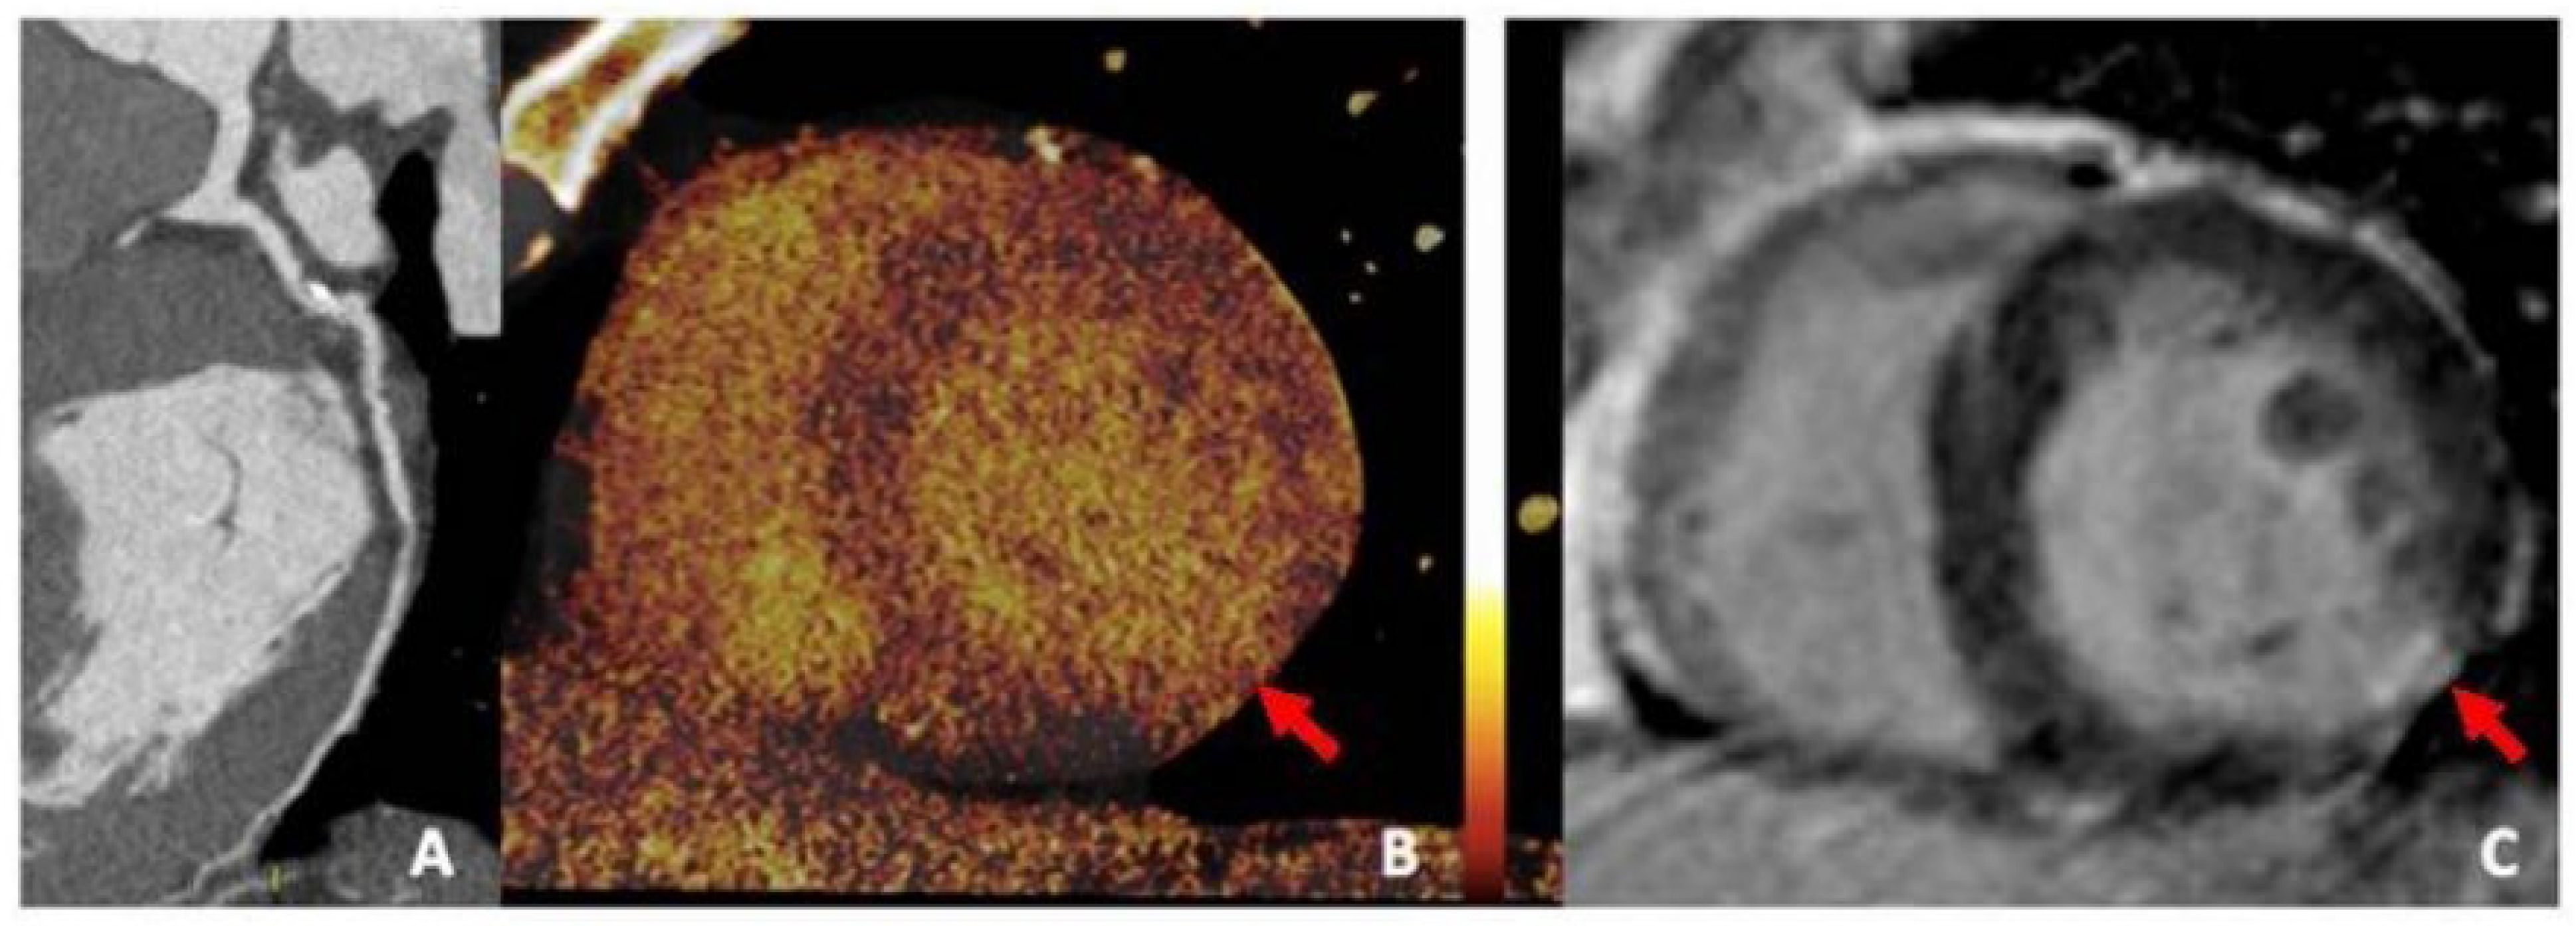

6.2. Positron Emission Tomography

The high spatial resolution and accuracy that imaging studies such as positron emission tomography (PET) (Figure 11) have, while utilizing fluorine isotopes to identify high-risk calcium plaques earlier in their progression, is better than CCTA because of the lower thresholds (200–500 µm) that the PET scan can operate on [48]. There is a relationship between 18F-NaF uptake and coronary calcification progression in stable CAD, as this molecular isotope represents a strong predictive marker for coronary artery calcification [56].

In addition to coronary artery disease, PET imaging utilizing 18F-NaF uptake has also been introduced in other vascular studies to examine other physical morphologies more effectively, including carotid atherosclerosis, abdominal aortic aneurysm (AAA) disease, aortic stenosis, bioprosthetic valve degeneration, and erectile dysfunction [57]. Lastly, the prognostic value of 18F-NaF uptake using PET-CT to assess coronary artery calcified plaques is currently being investigated through the ongoing prospective study, pioneered by the Prediction of Recurrent Events With 18F-Fluoride (PREFFIR) study [48].

6.3. Photon-Counting CT and Dual-Energy CT

Photon-counting CT (PCCT) (Figure 12) provides significantly superior imaging and diagnostic confidence in addition to the high quality of spatial resolution, soft-tissue contrast, and radiation dose efficiency while offering reduced partial volume averaging, better morphological depiction of CAC, and lower imaging noise [48,58]. Recent research has also shown that PCCT images have fewer blooming artifacts, less volume overestimation compared to micro-CT studies, and greater volume quantification accuracy with improved diagnostic quality of coronary calcifications [59,60].

Dual-energy CT (DECT) (Figure 13), also known as spectral CT, is another emerging imaging technique that provides high-quality anatomic information on CAC while enhancing plaque visualization and facilitating the accurate assessment of high-risk calcified plaques by combining information from both CT and the effective atomic number [61]. DECT enables the use of multiple virtual monoenergetic images to reduce blooming artifacts caused by highly dense calcifications, and it facilitates intracavity visualization by decreasing background noise, which is a limitation of CCTA [48,62].

PCCT possesses the intrinsic value and capability of computing and classifying photons, enabling spectral imaging to achieve higher spatial resolution while incorporating its advanced devices into cardiac-designed CT scanners [48]. This will lead to augmentation of a dual-source CT scanner with superior temporal resolution of approximately 66 milliseconds compared to an inferior single-source CT scanner with a temporal resolution of 120–125 milliseconds, which, when compared, will drastically reduce residual motion artifacts, leading to a more crisp, accurate, and precise physical morphology assessment of the coronary artery calcified plaques within the intraluminal vasculature [48].